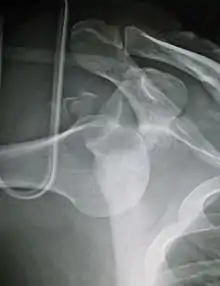

| Anterior dislocation of the left shoulder. | |

An anterior dislocation of the shoulder

Anterior dislocation of the right shoulder. AP X ray